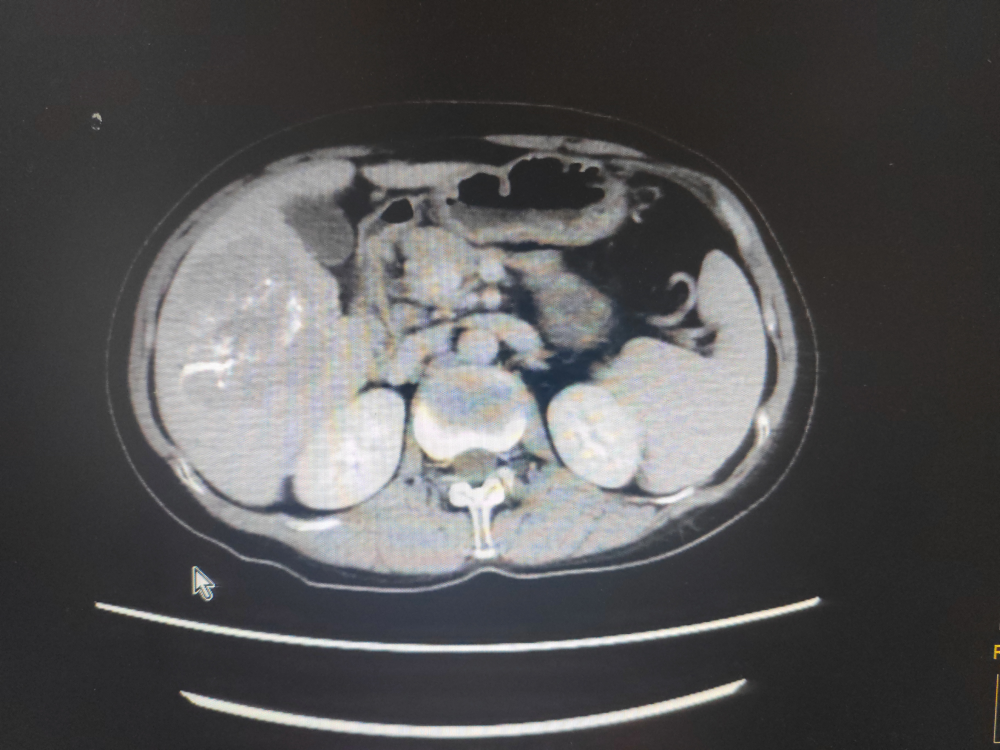

2023年4月15日上腹部增強CT